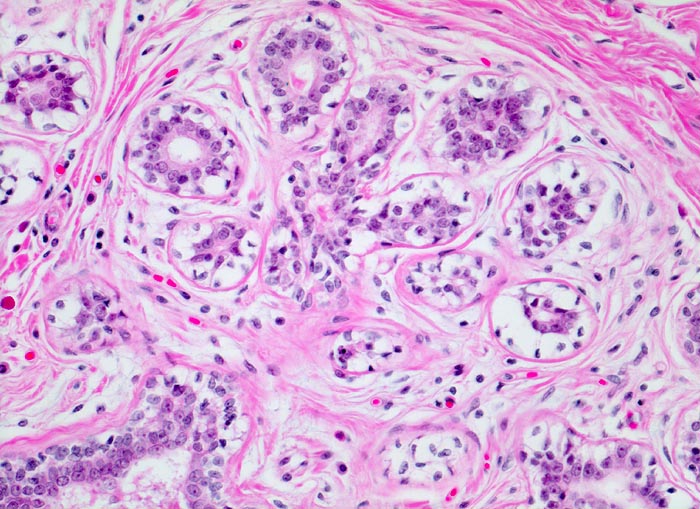

normale Mamma: terminale duktulolobuläre Einheit

Die terminale duktulolobuläre Einheit der Mamma umfasst einen intralobulären Ausführgang und zu einem Läppchen angeordnete Alveolen. Alveolen und Ausführgang werden vom gleichen zweischichtigen Epithel ausgekleidet. Das intralobuläre kollagenfasrige Gewebe ist etwas lockerer als das extralobuläre.

200